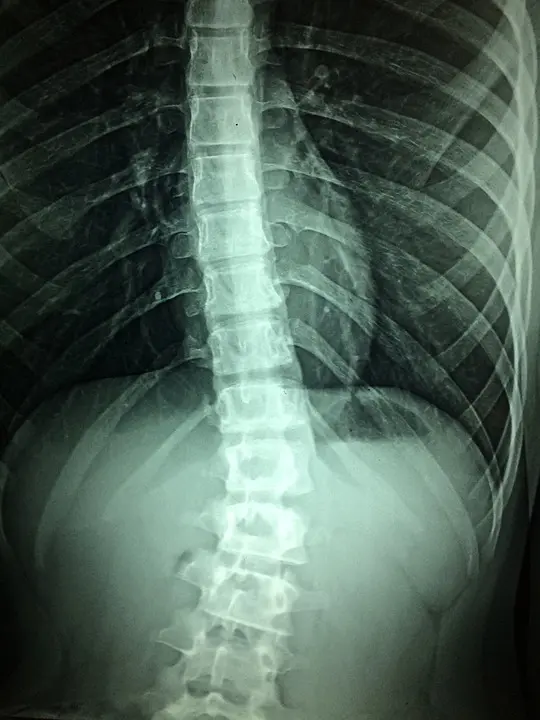

Anyone who experiences significant trauma to the head or neck is at risk for spinal cord injuries. These injuries are caused by damage to the spinal cord or to the nerves at the base of the spinal canal. They often compromise strength, sensation and other bodily functions below the site of the injury. The effects of spinal cord trauma may last long-term—even a lifetime in some cases.

(Pixabay / Taokinesis)